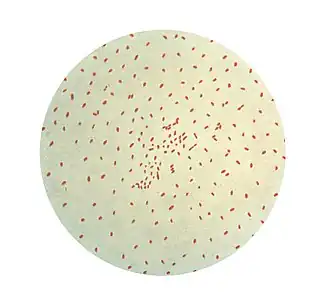

Bordetella pertussis (лат.) (бактерия Борде–Жангу, палочка коклюша, коклюшная палочка) — вид мелких неподвижных неспорообразующих аэробных грамотрицательных коккобацилл из рода бордетелл, вызывающий специфическое поражение эпителия бронхов, называемое коклюшем.

Бактерия неподвижна, оксидазоположительна, не вырабатывает уреазу, нитразу, не потребляет цитрат как единственный источник углерода. Образует характерные колонии типа «ртутной капли», которые крошатся при попытке снять их со среды.